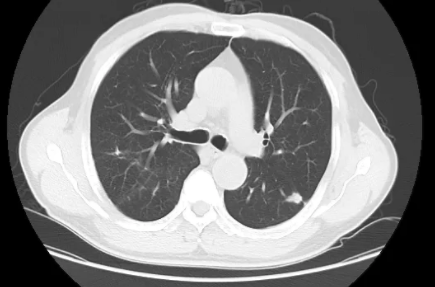

2.肺内生长类圆形、边界清楚、直径小于30mm的病灶称为肺部结节;

3.肺内生长类圆形、边界清楚、直径小于20mm的病灶称为肺部小结节,小于5mm的结节称为肺部微小结节。

(二)按照密度分类:

分为实性结节和亚实性结节,亚实性结节包含:纯磨玻璃结节和混合磨玻璃结节。